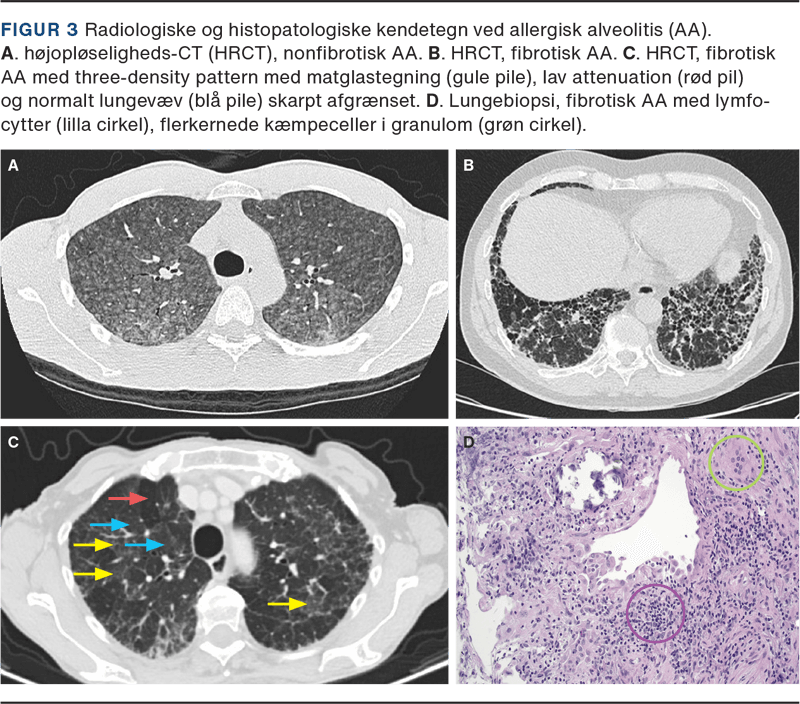

Billeddiagnostikken ved AA baseres på HRCT uden kontrast i to faser: den første under dyb inspiration, som viser infiltration af lungevævet, og den anden efter fuld eksspiration, hvor man vurderer lobulær air trapping.

Ved nonfibrotisk AA ses overvejende inflammatoriske og potentielt reversible forandringer, typisk som matglastegning og mosaikattenuering. Forandringerne er oftest symmetriske med diffus fordeling.

Ved fibrotisk AA ses fibrose med irregulær eller grov retikulering, varierende grader af inflammation og traktionsbronkiektasier i områder med matglastegning. Bikagetegning kan ses, men er ikke dominerende [16]. Fibroseforandringerne er oftest dominerende i midt- eller midt-/nedre lungezoner eller ligeligt distribueret i de tre lungezoner med relativt basal sparring. Hos begge typer AA ses forandringer, der indikerer small airways disease: vagt tegnede centrilobulære noduli og lobulær air trapping [17]. Ved fibrotisk HP ses three-density pattern med tydeligt afgrænsede hypo- og hyperattenuerede områder i kombination med normalt lungevæv (Figur 3).

Histologisk ses interstitiel, lymfocytær infiltration især omkring bronkiolerne, cellulær kronisk bronkiolitis og svagt definerede nonnekrotiserende granulomer. Ved fibrotisk AA er disse træk kombineret med interstitiel og luftvejscentreret fibrose [18].